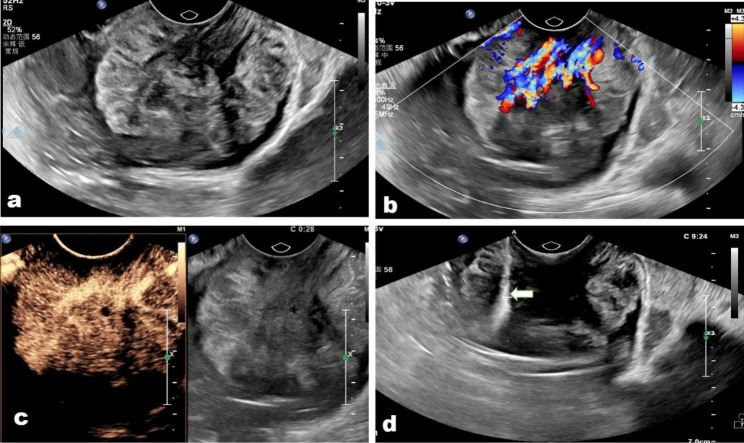

Fig. 4.

(a) A lower rectum rectal adenocarcinoma misdiagnosed as villous adenoma in a 48-year-old man. (b) The tumor showed abundant arborization vascular on color Doppler image; (c) the tumor presented regular hyper-enhanced on contrast-enhanced condition, and there were some minor necrosis areas in the tumor. (d) The biopsy needle (arrow) passes through the tumor center to acquire biopsy samples